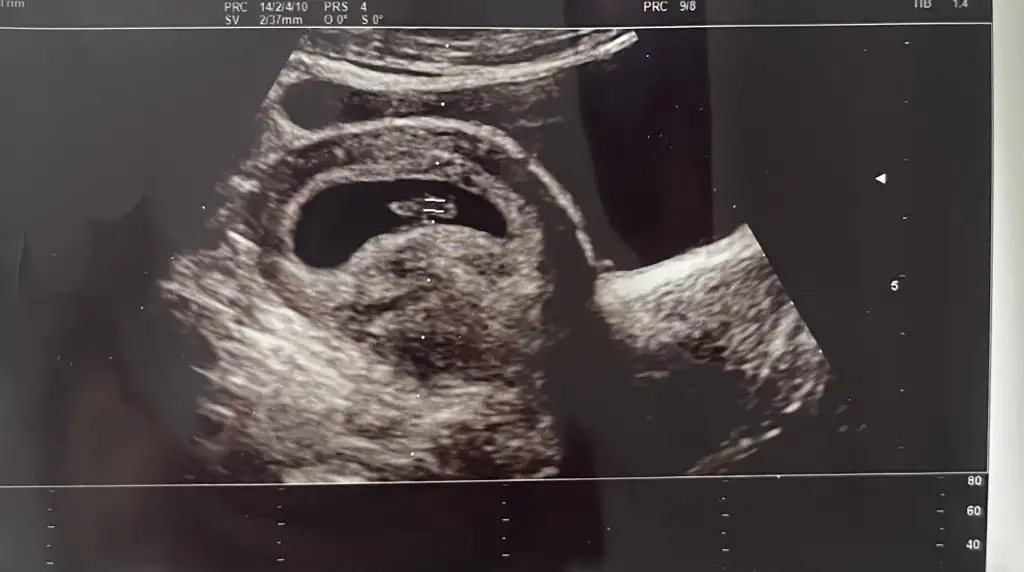

Kızlar sizce kesenin sol altındaki yuvarlak nedir, ilk ultrasonda da vardı daha küçüktü

Benim önceki gittiğimde vardı böyle minik bir şey doktor kanama Alanı ama küçük çok önemsiz dedi. Yine de progeston fitil başladı nolur nolmaz diye . Ciddi bir şey değildir sanırım ama yine de kendi doktorunuza gösterin❤️